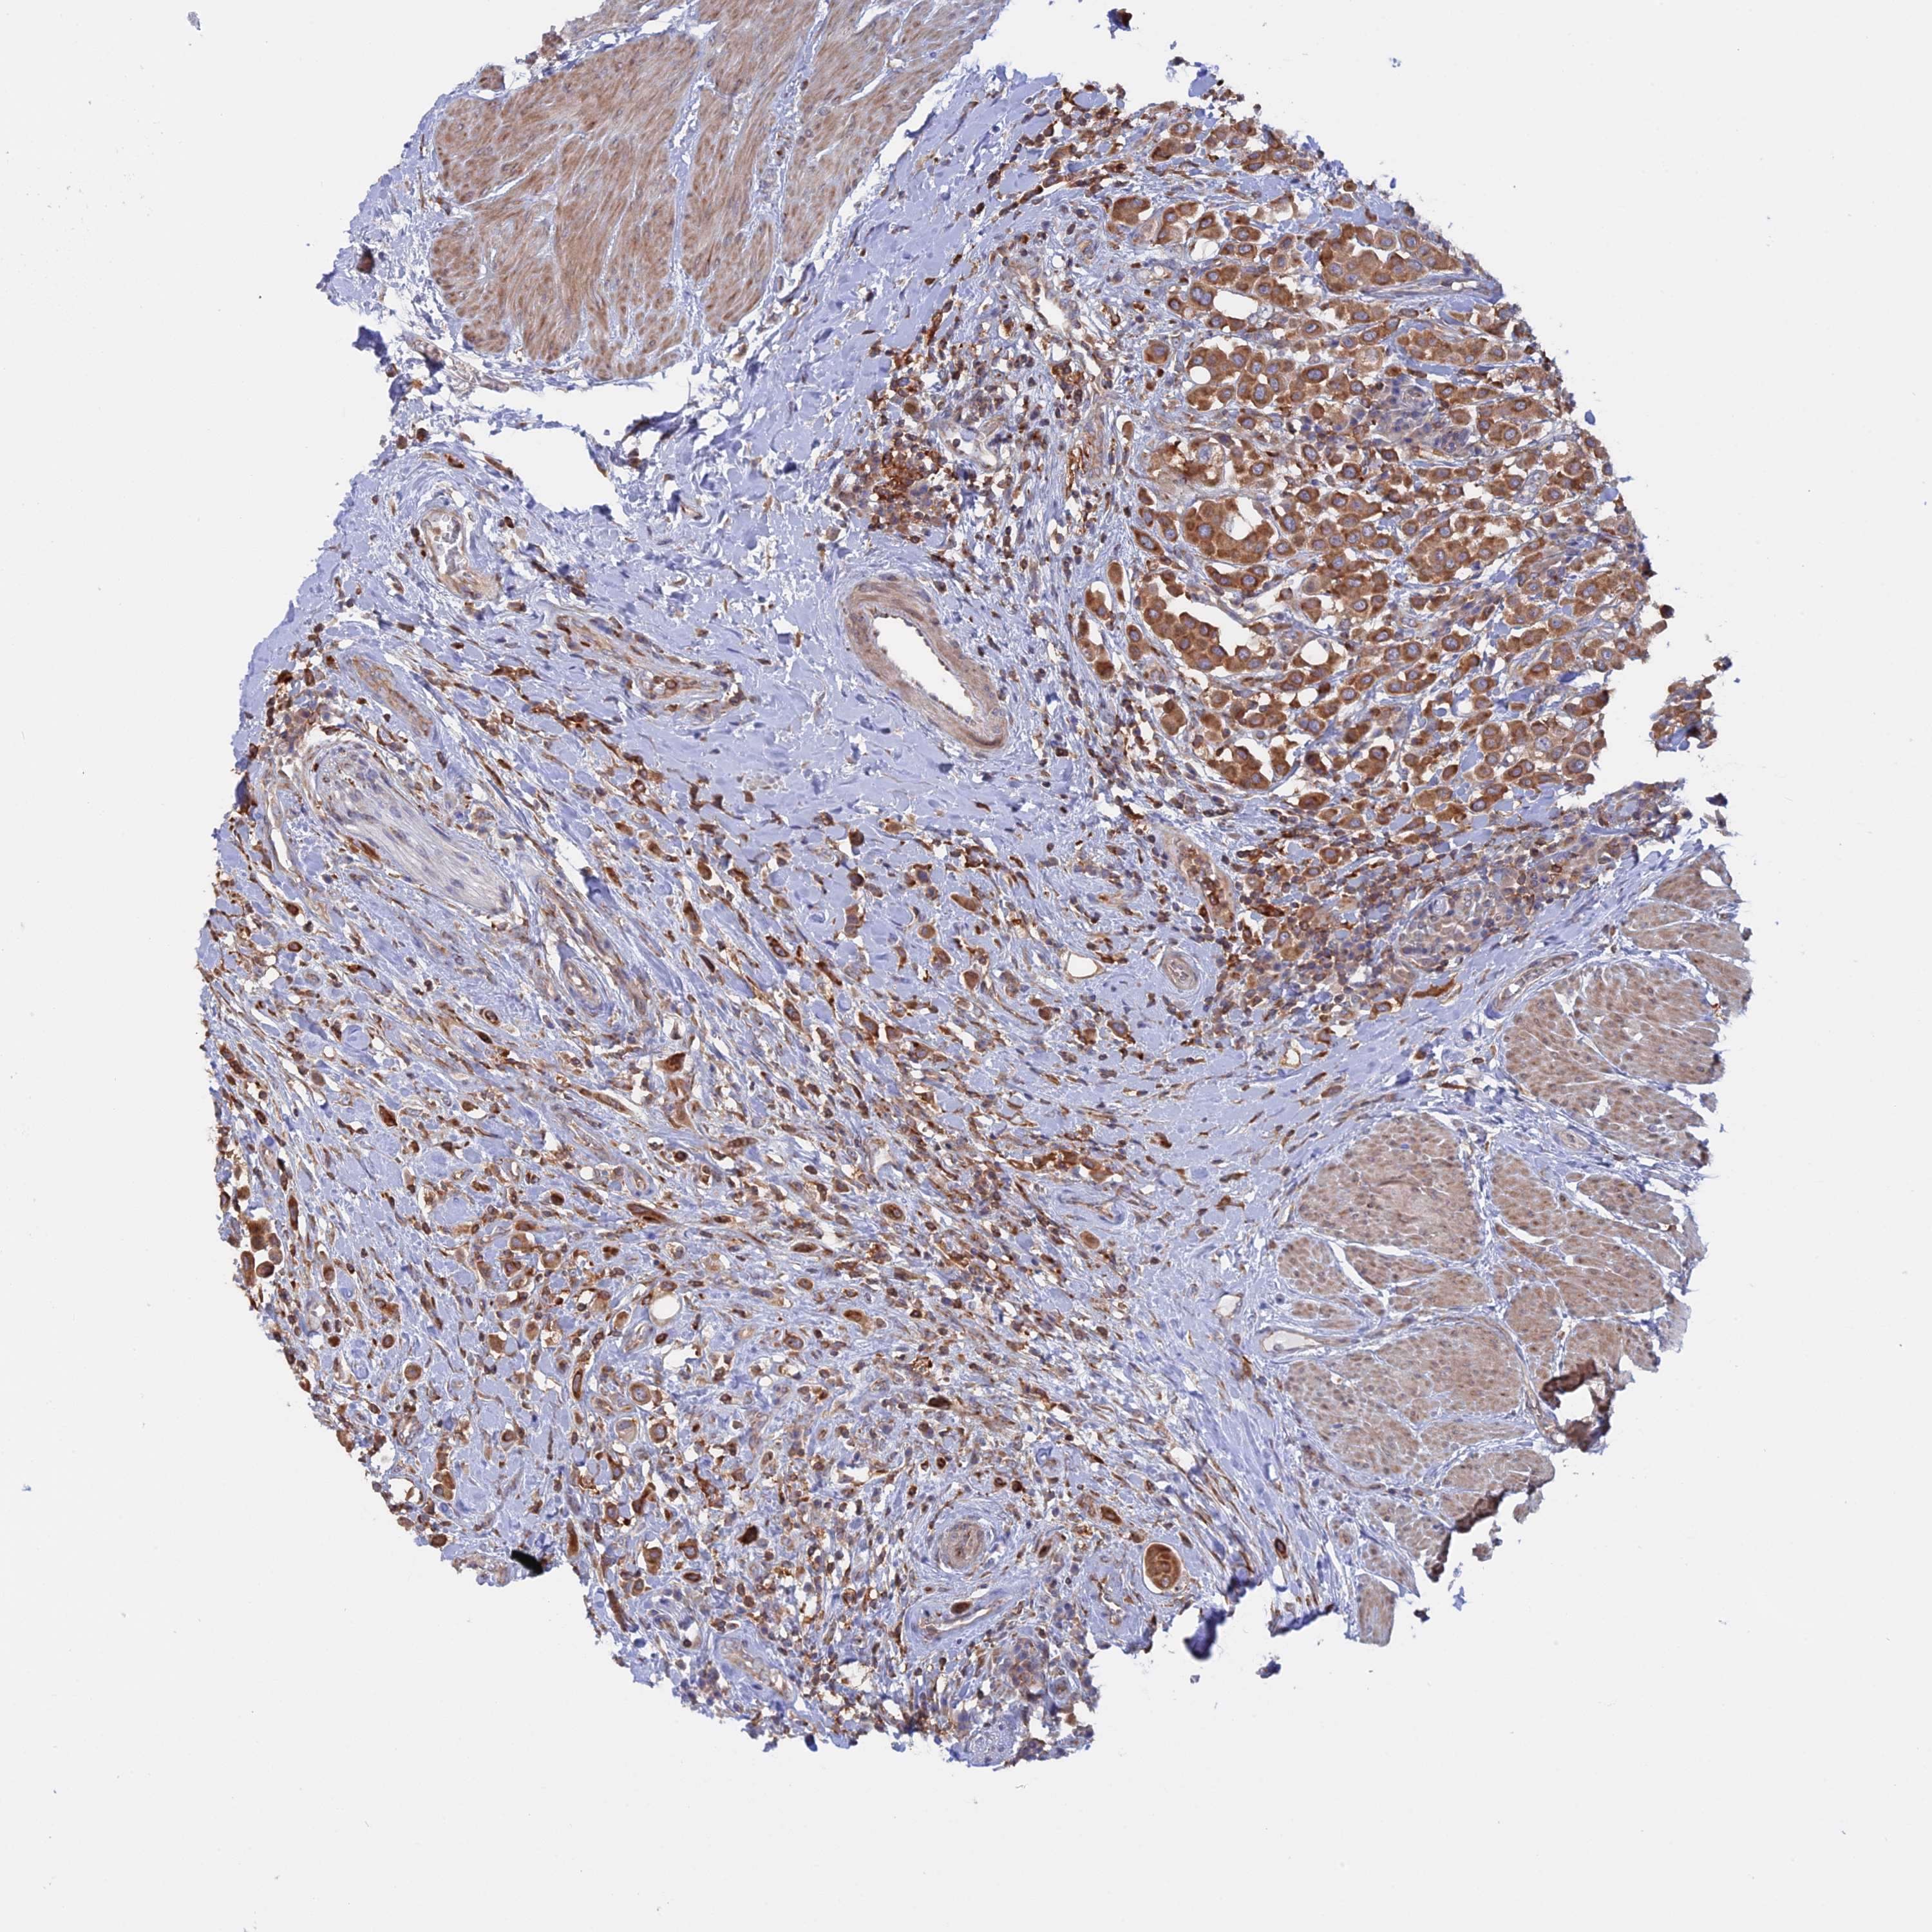

UROTHELIAL CANCER - Protein expressioni

A mouse-over function shows sample information and annotation data. Click on an image to view it in a full screen mode. Samples can be filtered based on level of antibody staining by selecting one or several of the following categories: high, medium, low and not detected. The assay and annotation is described here.

Note that samples used for immunohistochemistry by the Human Protein Atlas do not correspond to samples in the TCGA dataset.

Antibody stainingi

Antibody staining in the annotated cell types in the current human tissue is reported as not detected, low, medium, or high, based on conventional immunohistochemistry profiling in selected tissues. This score is based on the combination of the staining intensity and fraction of stained cells.

Each image is clickable and will lead to virtual microscopy that enables deeper exploration of all samples and also displays staining intensity scores, fraction scores and subcellular localization as well as patient and tissue information for each sample.

Antibody HPA042484

Antibody HPA045481

Staining

High

Medium

Low

Not detected

Intensity

Strong

Moderate

Weak

Negative

Quantity

>75%

75%-25%

<25%

None

Location

Nuclear

Cytoplasmic/membranous

Cytoplasmic/membranous,nuclear

Urothelial carcinoma, High grade

Urothelial carcinoma, Low grade

Urothelial carcinoma, NOS